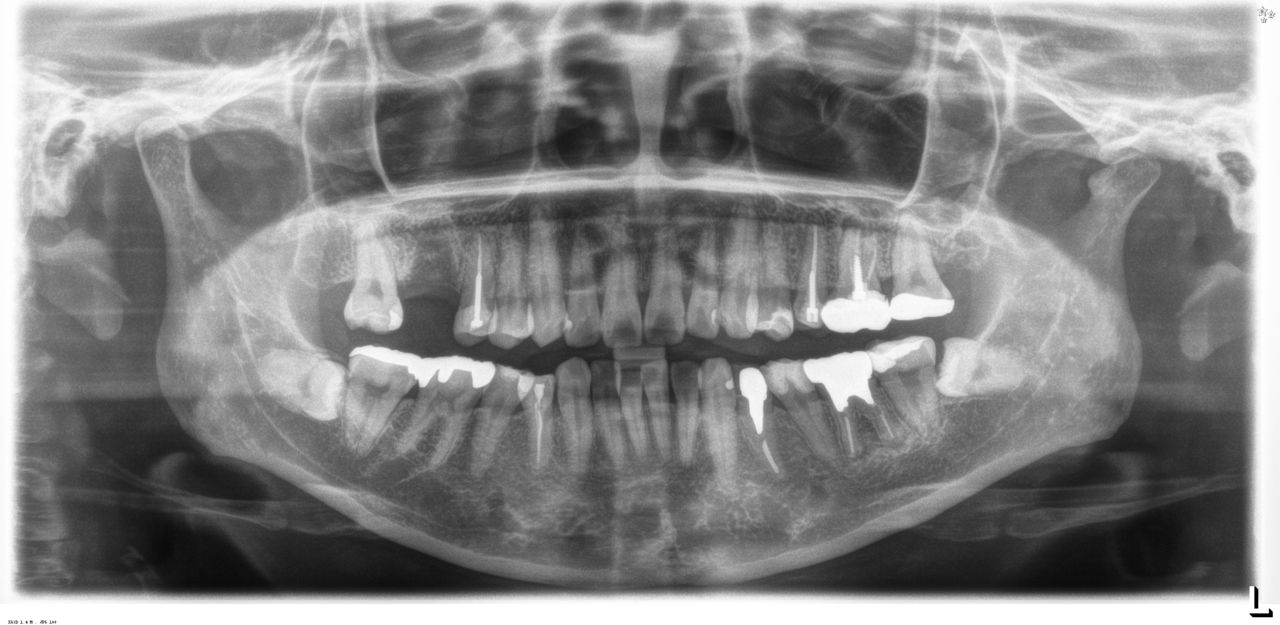

完成後のレントゲン写真

最終的な被せ物を装着した状態のレントゲン写真。

(今回は下顎ですが、その前に上顎は治療済みです。)

レントゲン写真